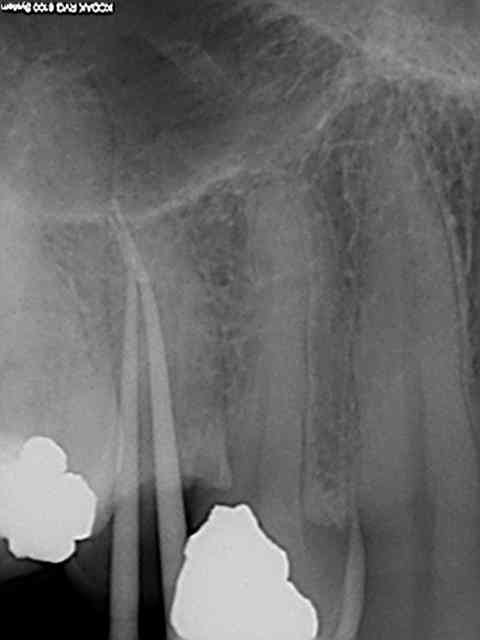

les pivotmatics sont calibrés pour 10 mm (rouge) ou 11 mm (bleu)de logement de tenon. C'est un peu emmerdant lors du mordu que le pivomatic touche l'antagoniste. Leur diamètre en outre sont supérieurs au largo 3. Ça fait des années que je procède de la sorte, les fractures de racines sont exceptionnelles contrairement aux fractures de cuspides vestibulaires ou palatines consécutives à des obturations MOD comme la 15 ci-dessus. Maintenant si tu as une technique fiable pour faire tenir des restaurations avec des pivots de 3 mm et d'un diamètre inférieur je suis preneur.)

Précision, j'utilise le largo 3 sur un contre angle double bague verte. Ça a son importance, pas tourner trop vite ni forcer of course.

Ca va on le voit bien à l'oeil nu le mv2 ? rendez vous de 30 mn, et oui consult (douleur sous gros amg), un peu just pour faire l'empreinte et la taille dans la séance, dommage . Pas facile de zoomer avec une seule main avec l'iphone par contre !))))